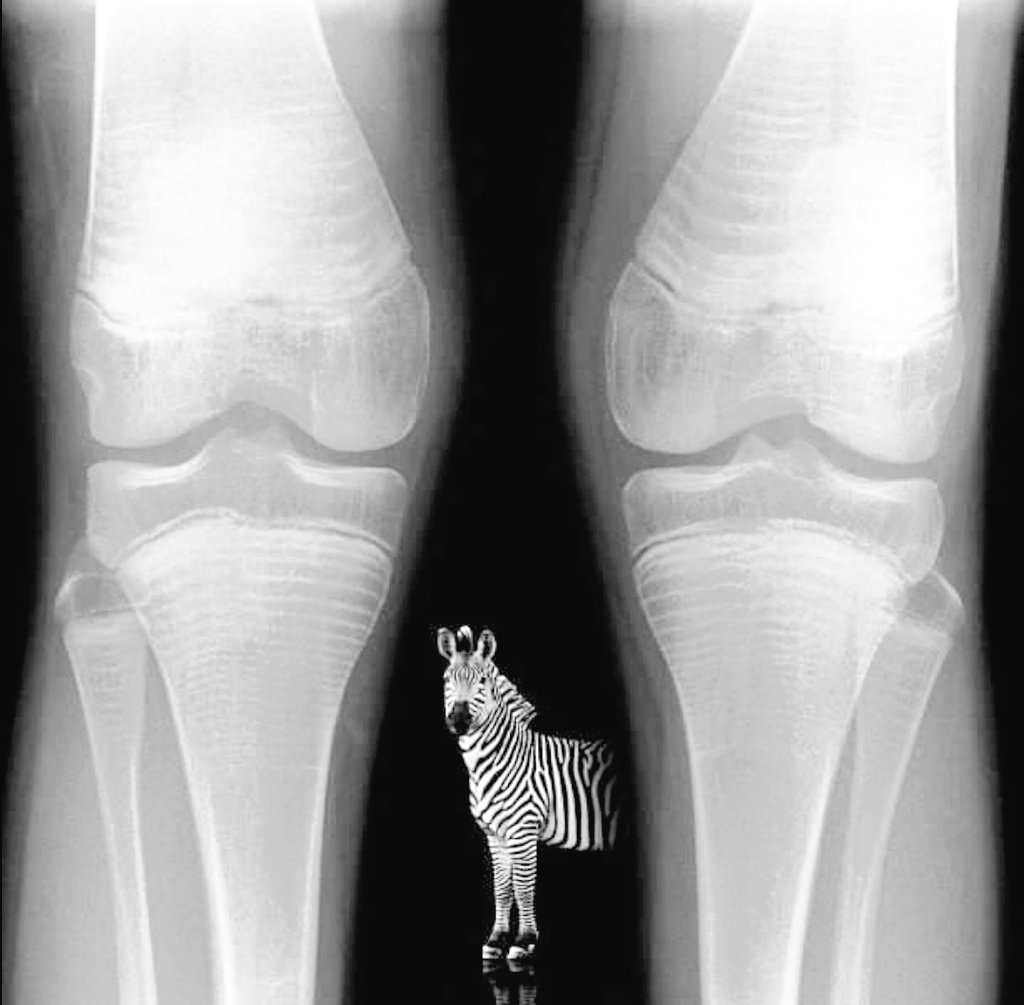

علامة الحمار الوحشي

Zebra stripe sign

تظهر كخطوط كثيفة وخفيفة لدى الاطفال الذين يعانون من خلل في تكون العظام و يخضعون لدورة علاجية